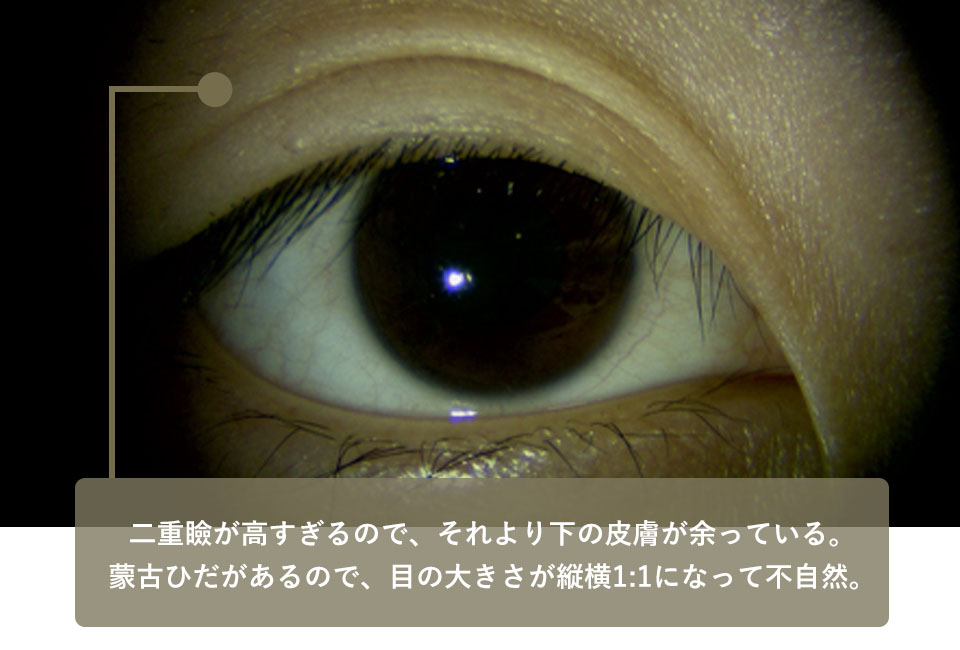

1年前に大手D美容外科で埋没法の手術を受けたが、術後に眼瞼の形状が不自然になってしまったので修正希望で来院。この方も症例2と同様に重瞼の位置が高すぎるので重瞼よりも下の皮膚がたるんでしまっています。

もう一つ、問題があります。それは内眼角贅皮という目頭の皮膚が張り出していることです。これは蒙古ひだともいわれるものでアジア人とくに東アジア人に多くみられるものです。

蒙古ひだが張ってしまっているので、いくら上眼瞼を綺麗に仕上げても、下に引っ張られてしまう以上、綺麗な重瞼線にはなりません。

このためこの方には内眥形成術(目頭切開)と上眼瞼の皮膚切除、重瞼作成を行いました。術後、平行型の綺麗な重瞼線が出来て表情も自然になりました。

| 術前 | 二重瞼の位置が上過ぎて結局その下の皮膚がたるんでいる蒙古ひだが張っているタイプなのでここを修正しないと自然な二重瞼にならない |

|---|---|

| 術後 | 皮膚を切除し低い位置で重瞼を作り直し、内眥形成(目頭切開)も行うことで平行型の重瞼が出来た |

| 術前 | 二重瞼が高すぎるのでそれより下の皮膚が余っている蒙古ひだがあるので、目の大きさが縦横1:1になって不自然 |

|---|---|

| 術後 | 内眥形成と重瞼の作り直しをしたところ、目の大きさの比は縦横1:2くらいの自然な大きさになった |